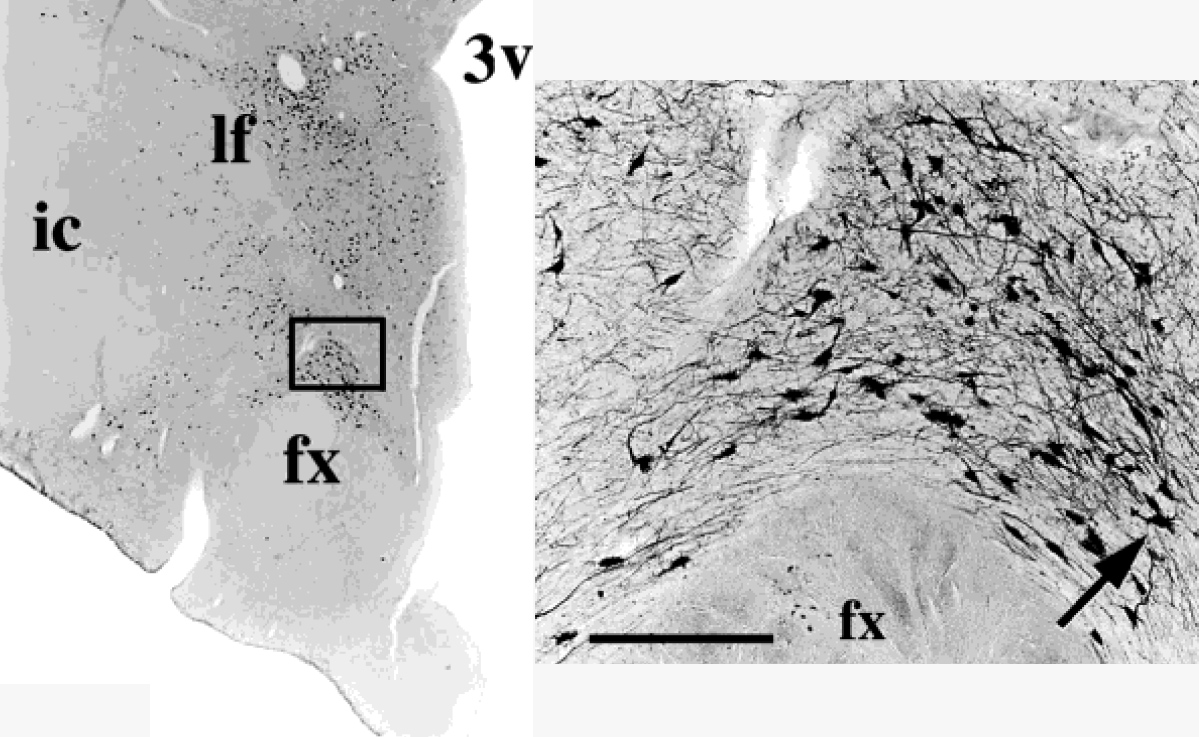

Neurons in a human brain stained immunohistochemically for melanin-concentrating hormone

Many of the circuits we study in animals also contain the same neurotransmitters in humans. We use immunohistochemical staining to study these neurons in human post-mortem brains, and to determine how these neurons are affected by Alzheimer's, Parkinson's and other neurodegenerative diseases.